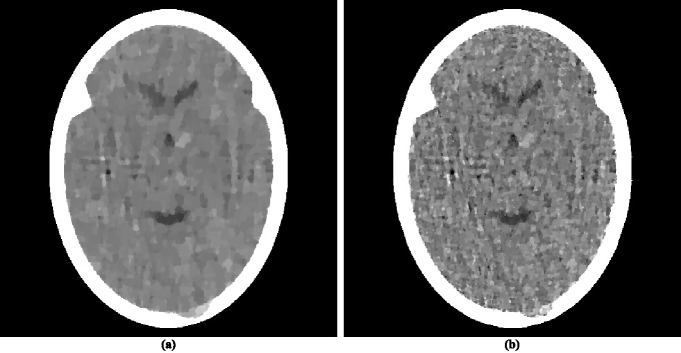

It has been mentioned in Subsection II.2 that except for the presence of in (3), which enforces nonnegativity of the components, is identical to the algorithm used and illustrated in HERM08a (31). It is known that CT reconstruction of the brain from many views does not suffer from ignoring the fact that the components of the , which represent linear attenuation coefficients, should be nonnegative; as is illustrated in figure 1(b). This remains so when reconstructing from a few views using the method and data that we have been discussing: if we do everything in exactly the same way as was done to obtain the reconstruction with value 826 that is shown in our figure 2(b) but remove from (3), then we obtain a reconstruction in figure 4(a) whose value is 829.

Another variation that deserves discussion, because it has been suggested in the literature PENF10a (22), is one that does not come about by making choices for the general approach of the Superiorized Version of Algorithm but rather by changing the nature of the approach. The variation in question is not applicable in general, but can be applied to the special case when the algorithm to be superiorized is the defined by (3). It was suggested as an improvement to the approach presented above with the choice . The idea was based on recognizing the block-iterative nature of the algorithmic operator in (3) and intermingling the perturbation steps of lines (vii)-(xvii) of the Superiorized Version of Algorithm with the projection steps of (3). It was reported in PENF10a (22) that doing this is advantageous to using the Superiorized Version of Algorithm . However, when we applied the variation of the Superiorized Version of Algorithm that is proposed in PENF10a (22) to the problem that we have been using in this section, we ended up with the reconstruction in figure 4(b) whose value is 920. This is not as good as what was obtained using the version of the algorithm that produced the reconstruction in figure 2(b). We conclude that the variation suggested by PENF10a (22), which does not fit into the theory of our paper, does not have an advantage over what we are proposing here, at least for the problem that we have been discussing in this section. We conjecture that the improvement reported in PENF10a (22) is due to selecting using subgradients as discussed in the paragraph following (7) and, as discussed earlier, such an improvement is not obtained if is selected by the more appropriate method recommended in this paper.